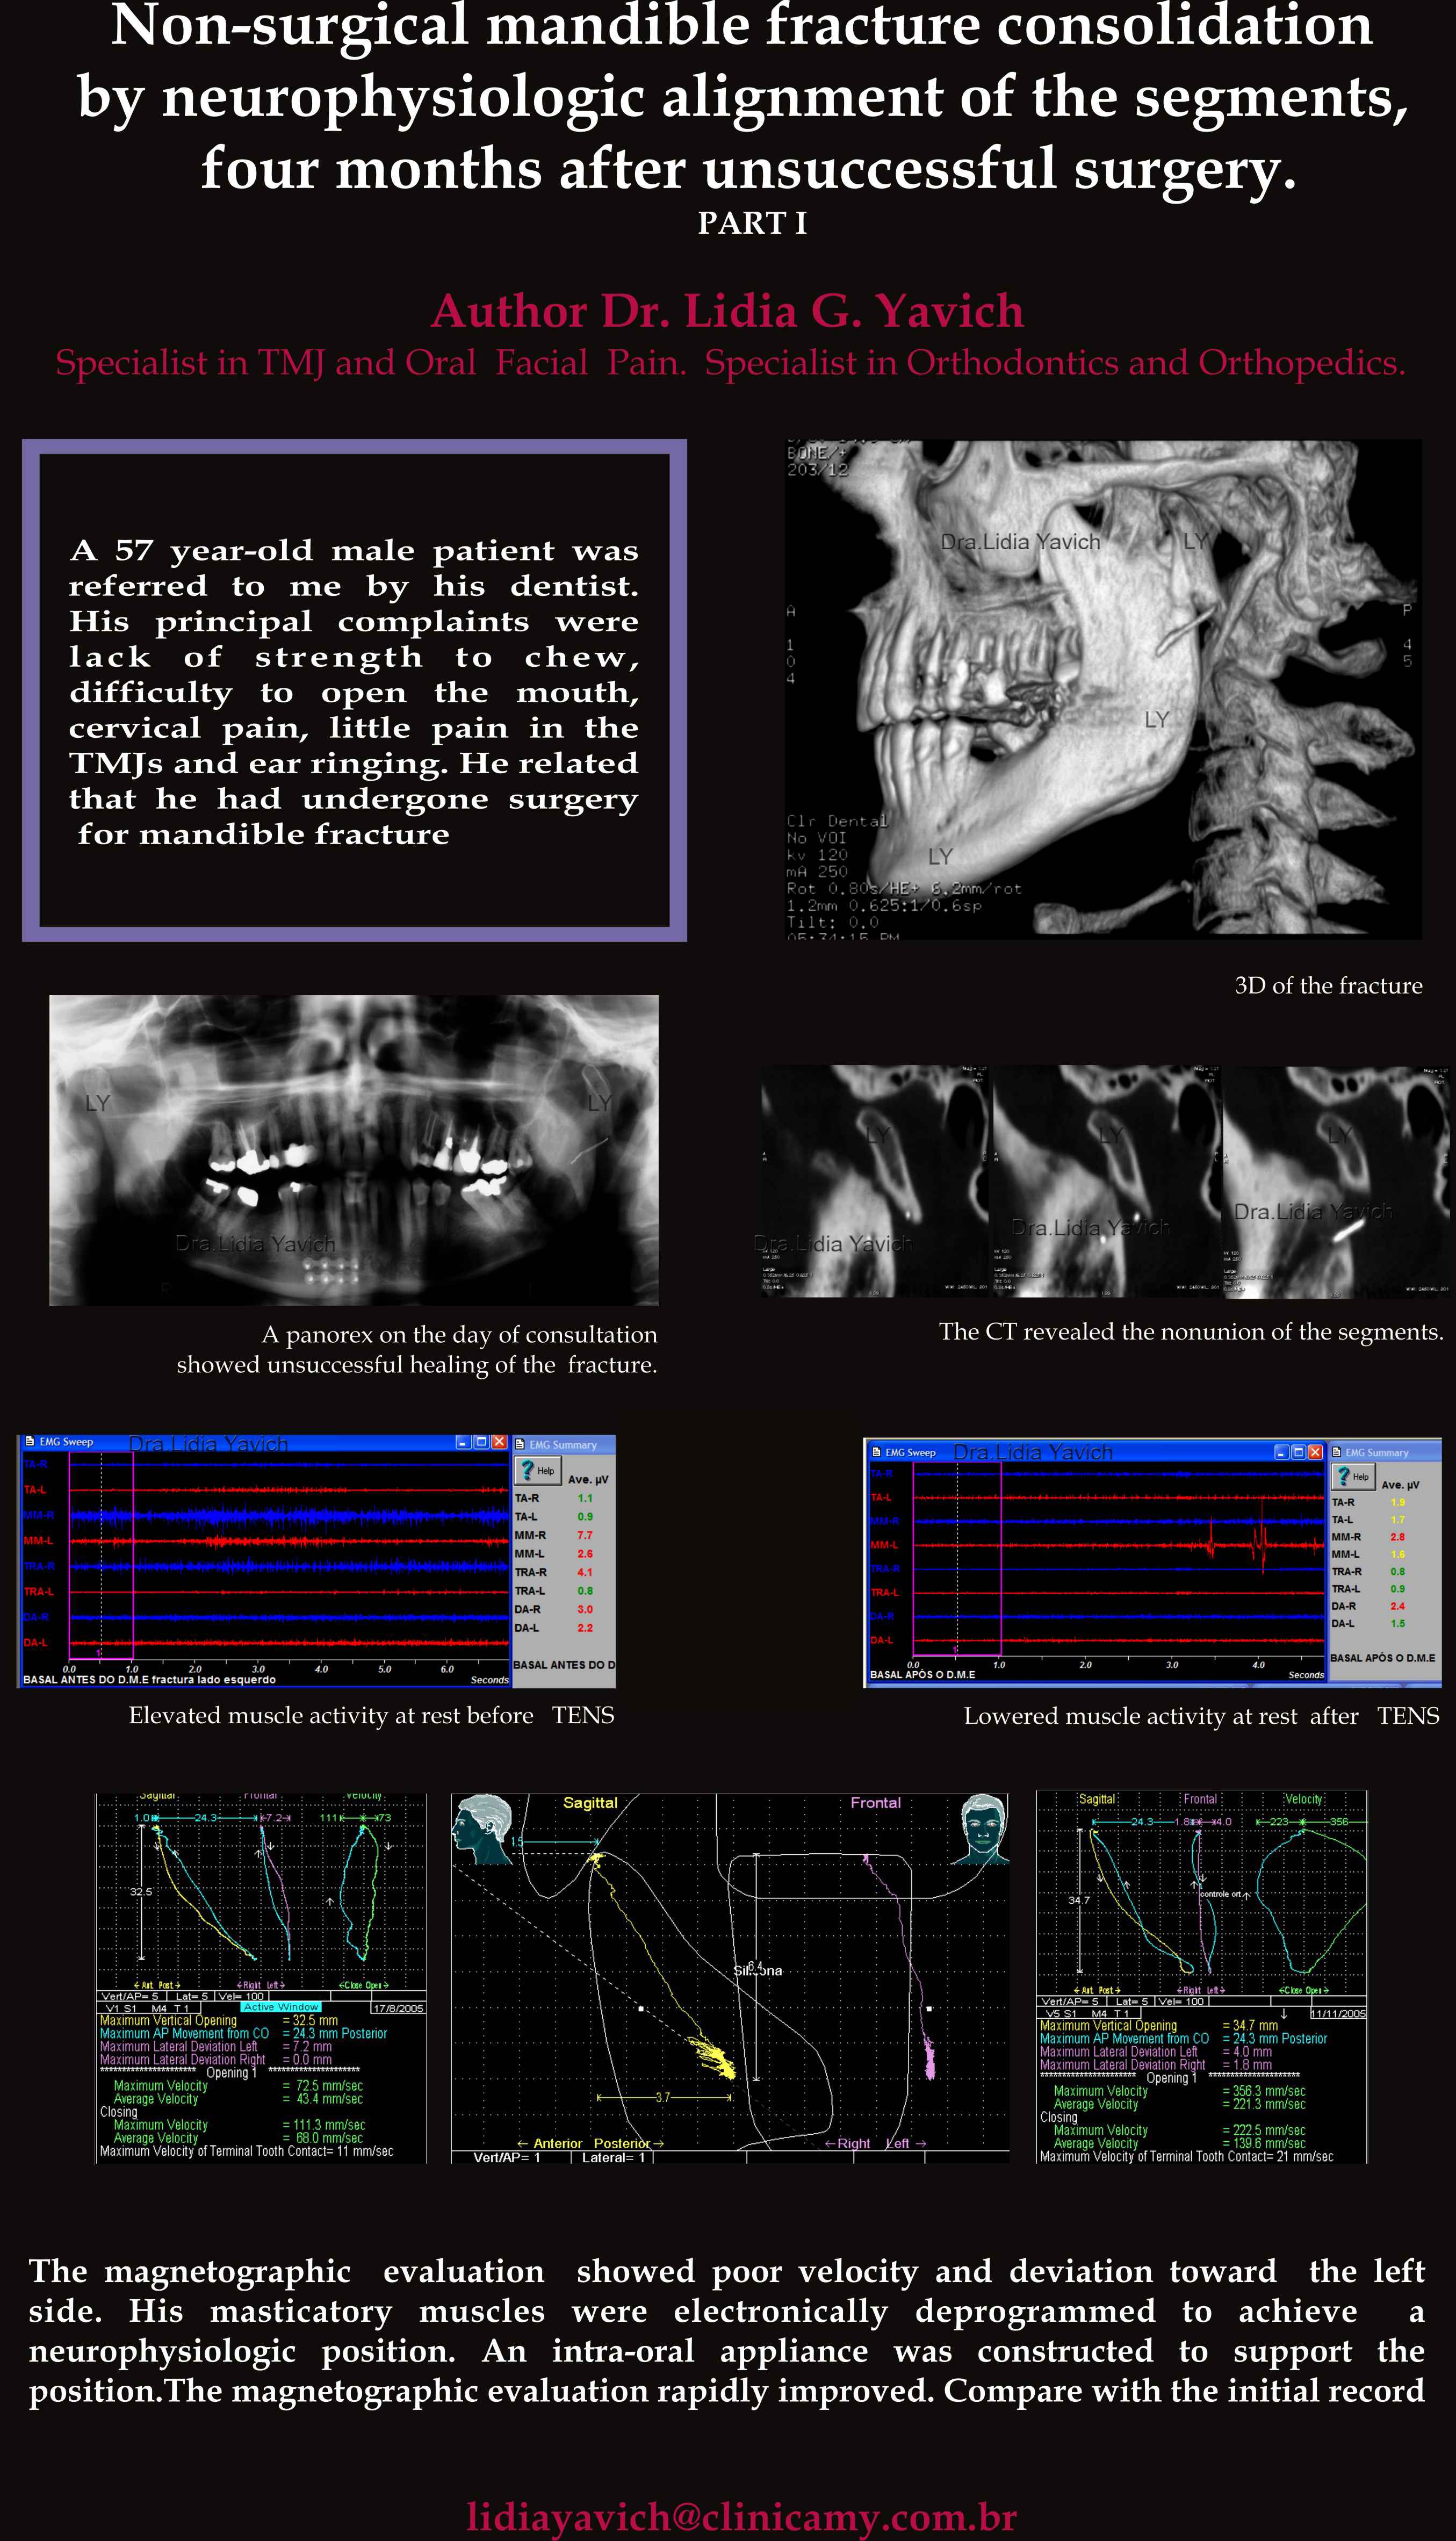

Após a realização de todas as avaliações clínicas foi solicitado uma radiografia panorâmica. Foi evidente a falta de união da fratura do côndilo mandibular esquerdo.

Côndilos mandibulares assimétricos. Imagem radiopaca compatível com fio de osteosíntese na região inferior da apófise condilar do lado esquerdo com deslocamento do fragmento ósseo.

Na região do mento do lado direito, imagens radiopacas horizontais compatíveis com artefatos de osteosíntese para contenção da fratura na região anterior da sínfise mentoniana.

Ampliação do côndilo mandibular esquerdo na radiografia panorâmica.

Laminografia das ATMs do paciente no dia da consulta evidenciando a falta de união da fratura do côndilo mandibular esquerdo.

Foi solicitada uma TC (tomografia computadorizada) para obter um diagnóstico mais preciso.

TC: cortes sagitais confirmando a falta de união total da fratura do côndilo mandibular, quatro meses após a cirurgia.

TC: cortes frontais confirmando a falta de união total da fratura do côndilo mandibular, quatro meses após a cirurgia.

Reconstrução em 3D mostrando a falta de união total da fratura do côndilo mandibular, quatro meses após a cirurgia.

Outra reconstrução em 3D mostrando a falta de união total da fratura do côndilo mandibular, quatro meses após a cirurgia.

Registro eletromiográfico antes da desprogramação eletrônica na primeira consulta: atividade elevada do masseter direito, do trapézio direito e do digástrico direito em repouso.

Todos estes músculos mastigatórios abaixaram os seus valores após a desprogramação eletrônica.

Diminuição da atividade dos músculos mastigatórios em repouso após a desprogramação eletrônica.

Registros eletromiográficos comparativos antes e após a desprogramação eletrônica na primeira consulta do paciente.